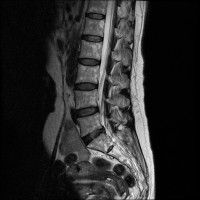

경추 요추 디스크 둘다 있는 상태고 경추몇번에서 몇번사이 요추몇번에서 몇번사이인지 알려주세요

허리

• 2번 째 사진